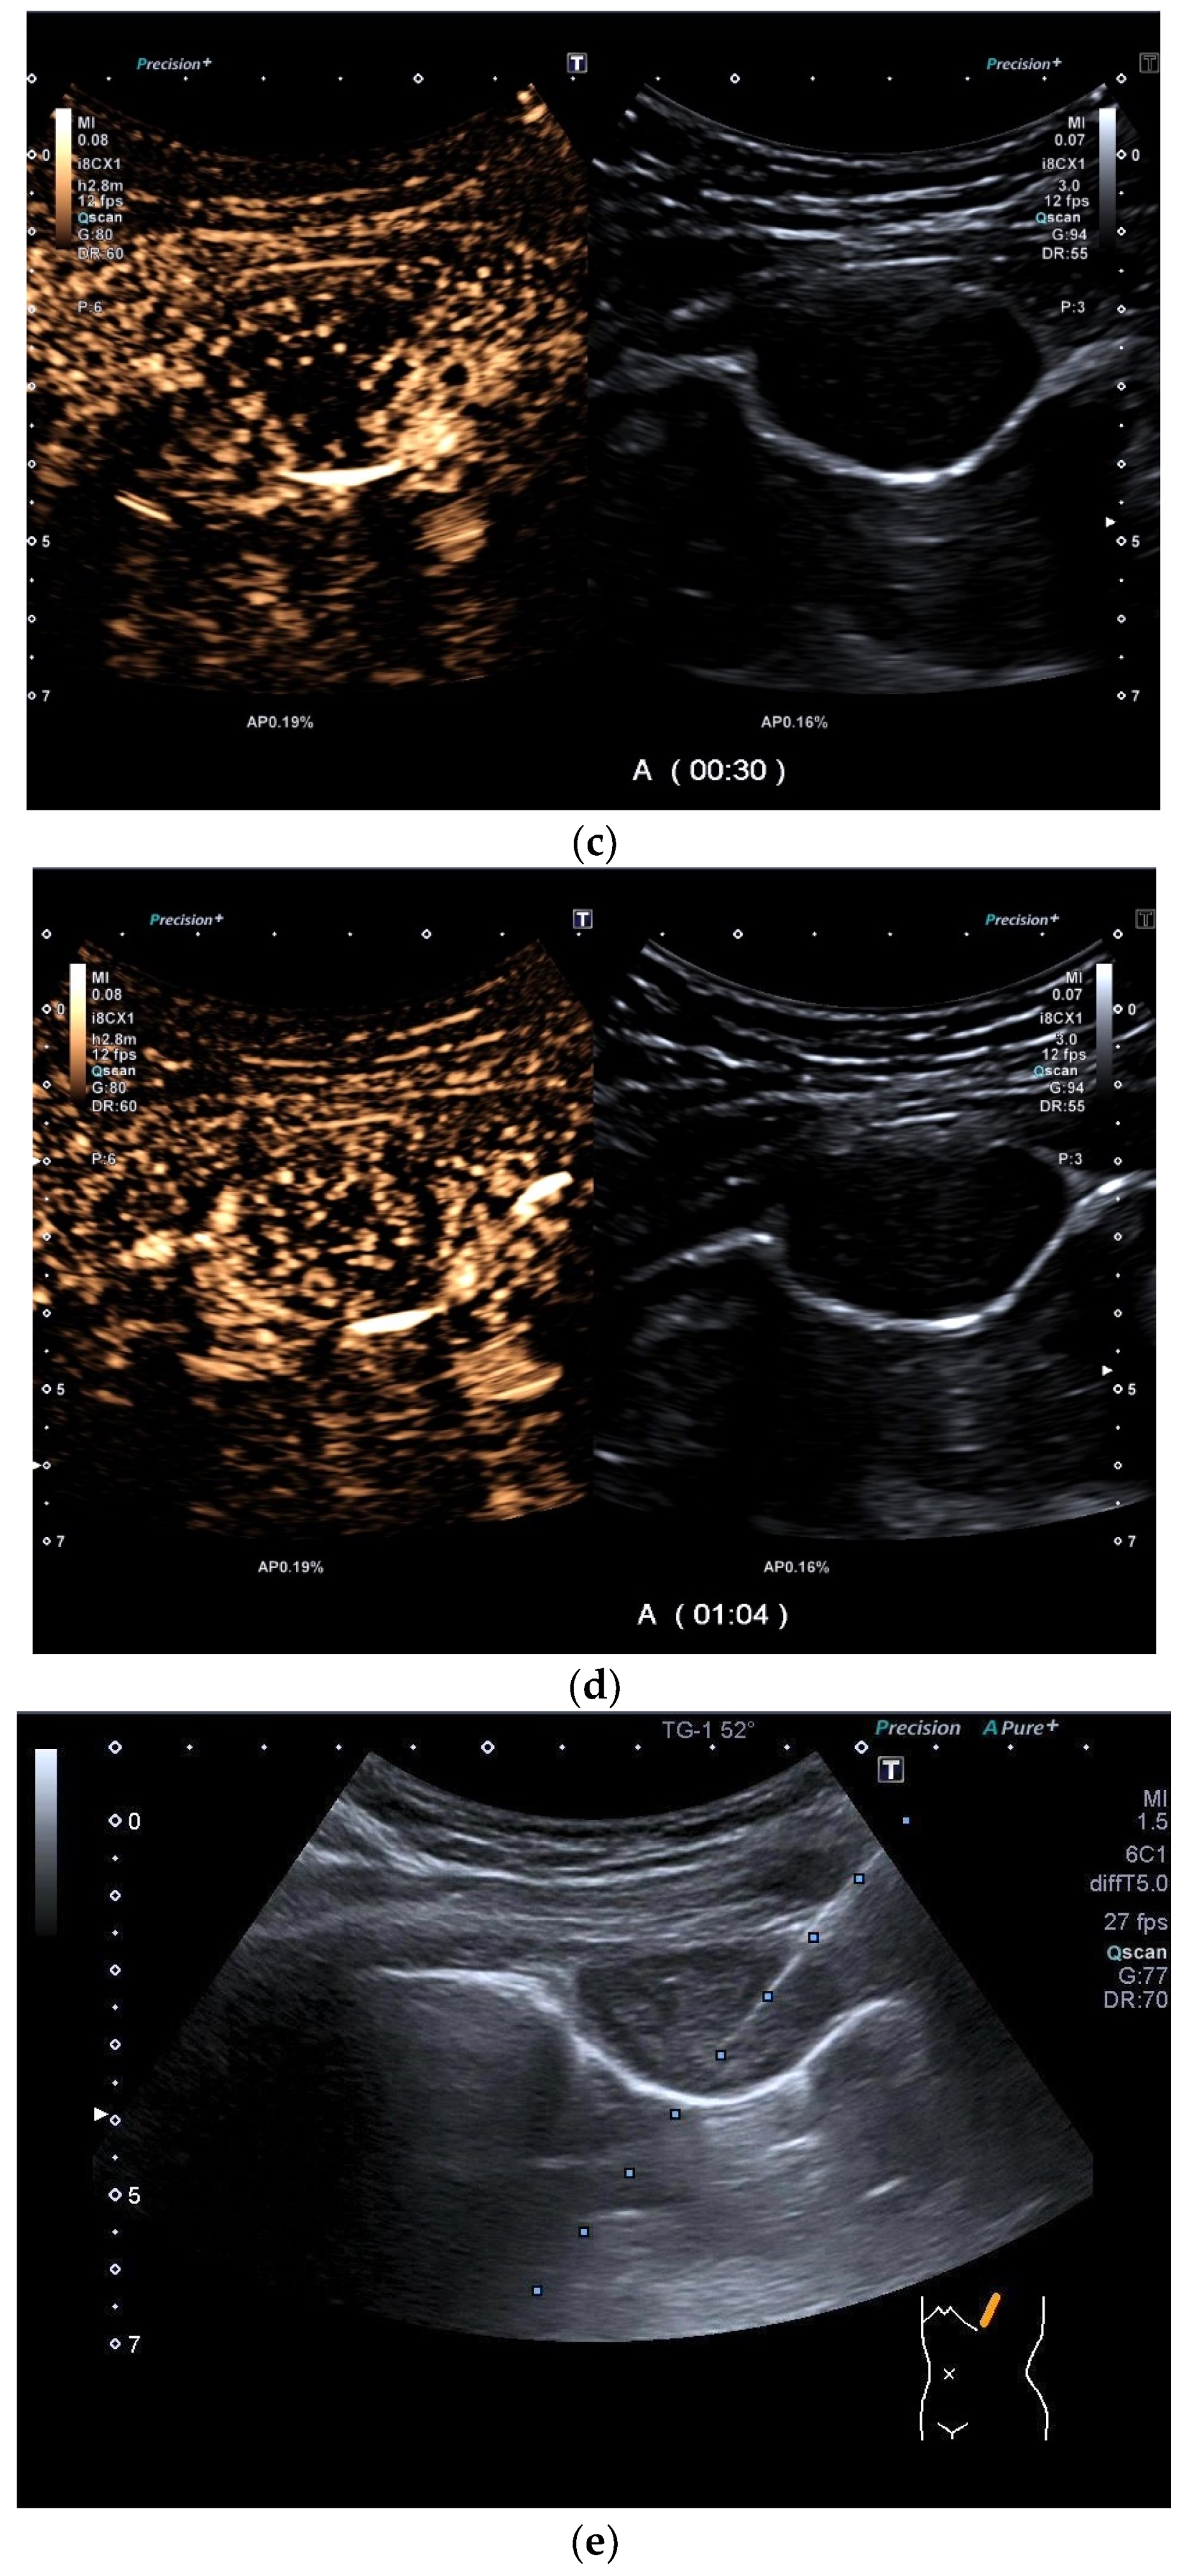

| Tuberculous pleuritis | Pleura effusion with fibrin strands, pleural calcification, and thickening. Hypoechoic granulomatous inflammation and granulomas with hyper-enhancement on CEUS in thickened pleura. Hypoechoic caseous abscesses in thickened pleura, hypo- or nonenhanced, heterogeneously enhanced lesions, with contrast-enhanced septations and contrast-enhanced rim. |